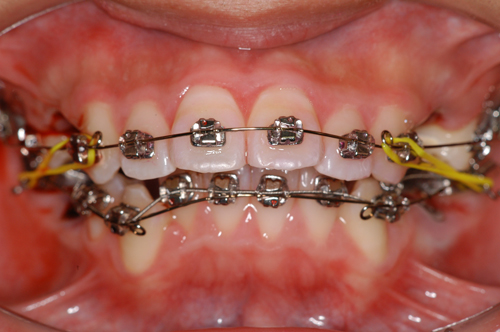

患者:14歳8ヶ月 男性

抜歯部位:上顎、第一小臼歯 下顎第二小臼歯

動的治療期間:18ヶ月